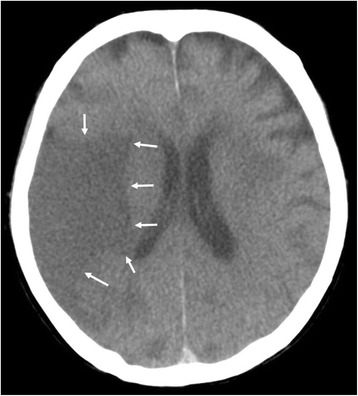

PMI findings

Multiple LDAs were recognized in the right middle cerebral artery (MCA) region (Fig. 1), right cerebellum, and left basal ganglia on PMI. They seemed to be infarctions. Since no atrophy was found in the brain, the infarctions seemed to be relatively fresh lesions. There was neither a mass effect nor hemorrhage in the brain. The ground glass shadow was widespread in bilateral lungs, and part of the lungs showed infiltrative shadow and the crazy paving pattern. As the cause of the interstitial shadow, adult respiratory distress syndrome (ARDS), acute interstitial pneumonia, or an infectious disease such as Pneumocystis jirovecii pneumonia was considered. No airway obstruction was found. A cardiac pacemaker was confirmed. Neither brain CT nor brain MRI was done during the patient’s lifetime.

Fig. 1.

Brain postmortem CT image 14 h after death (Case 1). An LDA was found in the middle cerebral artery area (arrows)